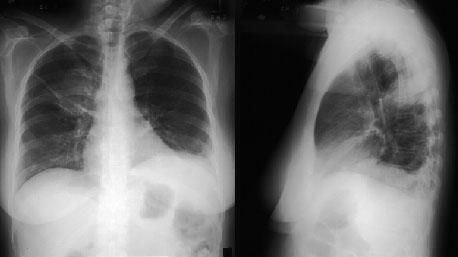

Рентгенография органов грудной клетки позволяет обнаружить затемнения или узелки в легких (в 75% случаев),узловатые и билатерально расположенные инфильтраты, которые крайне редко осложняются формированием асептической полости, затемнения симметрично расположены по периферии, признаки плеврального выпота.

Компьютерная томография высокого разрешения проводится с диагностической целью при необъяснимой одышке, выявлении рентгенологических изменений и снижении сатурации кислорода. С помощью этого метода можно визуализировать:

- паренхиматозные инфильтраты, часто схожие с феноменом «матового стекла», расположенные преимущественно по периферии;

- утолщение стенок бронхов; в отдельных местах дилатацию вплоть до образования бронхоэктазов;

- возможно выявление узлов в легочной ткани